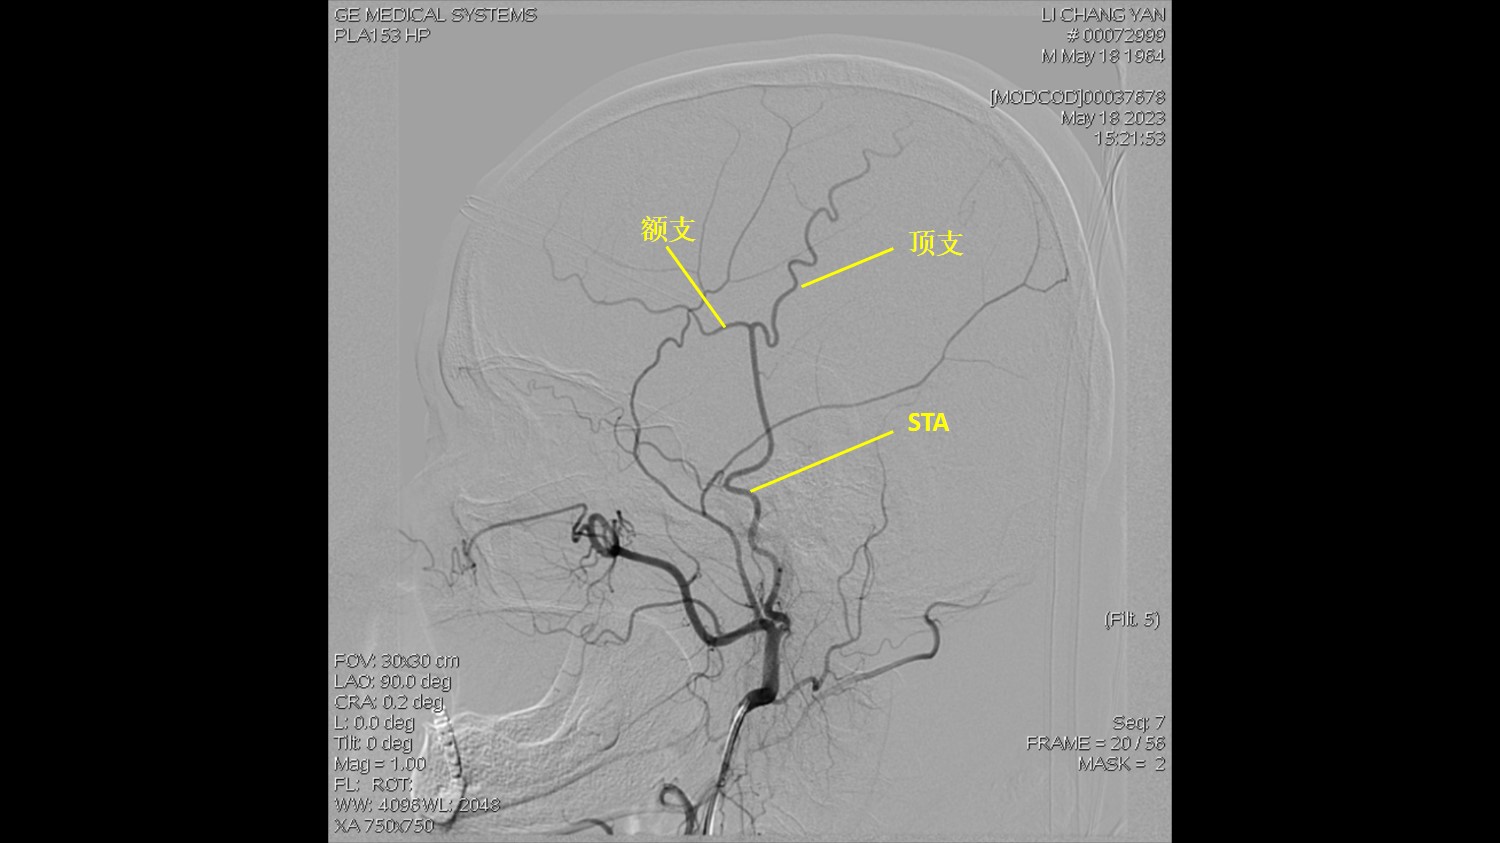

DSA显示:右侧MCA闭塞,依靠颅底软膜支、大脑前动脉代偿。

右侧ECA